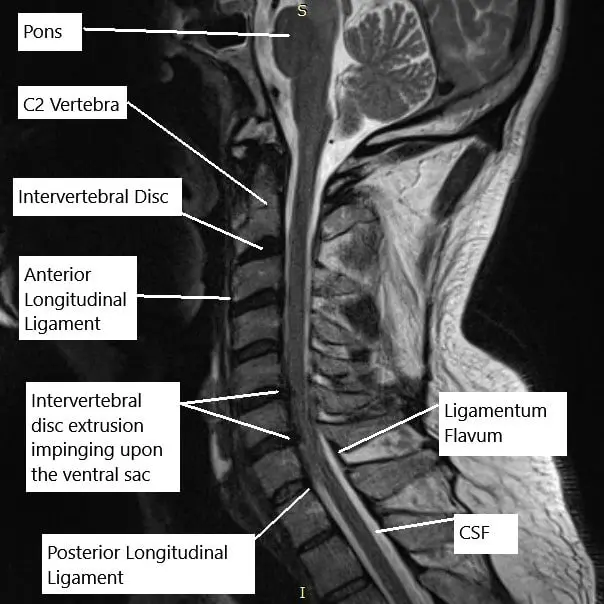

MRI of the cervical spine in the sagittal section.

The physical examination corroborated the MRI findings of the cervical spine which suggested at C5-C6, there is a posterior disc osteophyte complex. There is severe spinal canal stenosis and there is bilateral uncovertebral joint hypertrophy. There is moderate to severe right and severe left neural foraminal stenosis.

At C6-C7, there is a left paracentral disc herniation/extrusion creating impression on the ventral aspect of the thecal sac and spinal cord. There are severe associated spinal canal stenosis and bilateral uncovertebral joint hypertrophy. There is severe left-sided neural foraminal stenosis.